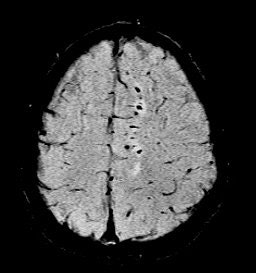

He also presented a trauma case comparing 2D conventional gradient-echo imaging (TE = 20 msec) and SWI. The patient had an accident and suffered subsequent cognitive impairment.

"This is where SWI lets you start seeing very small, almost pixel-like effects, probably microhemorrhages where there may be damage," he said. "Conventional gradient-echo imaging didn’t show any effects, but on the SWI you could see evidence of microhemorrhages and edema (see below). In most cases, you will see something with SWI that you won't see with conventional imaging. It could have significant impact in trauma imaging because you'd like to know what's wrong with them, and whether they are going to get better."

| Diffuse axonal injury in trauma. GRE image above; SWI image below. Data was collected on a 1.5-tesla scanner (Vision, Siemens Medical Solutions) with a TE = 40 msec and a resolution of 0.5 mm x 1.0 mm by 2.0 mm. Images courtesy of Dr. Karen Tong, Loma Linda University. |